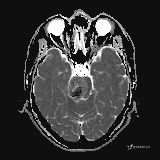

患者男,51岁。

简要病史:患者自述于1周前至某人民医院发现脑干肿瘤(具体不详),为求进一步诊断至我院就诊。

完善颅脑MRI平扫+增强,颅脑CT平扫:

T2: